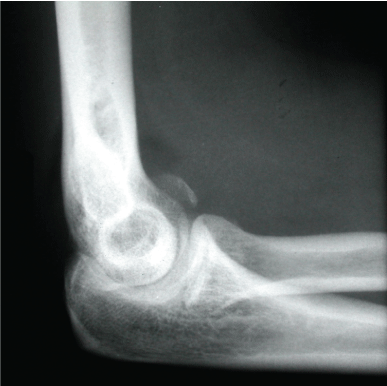

Case 2: Images 2a-g

A 34 year old patient after a fall from a chair with a Mason III fracture of the radial head and rupture of the anular ligament. Follow-up after 15 months: extension/flexion 0-0-140; pronation/supination 90-0-90. She received a score of 100 points according to Morrey and a score of good according to R & R.